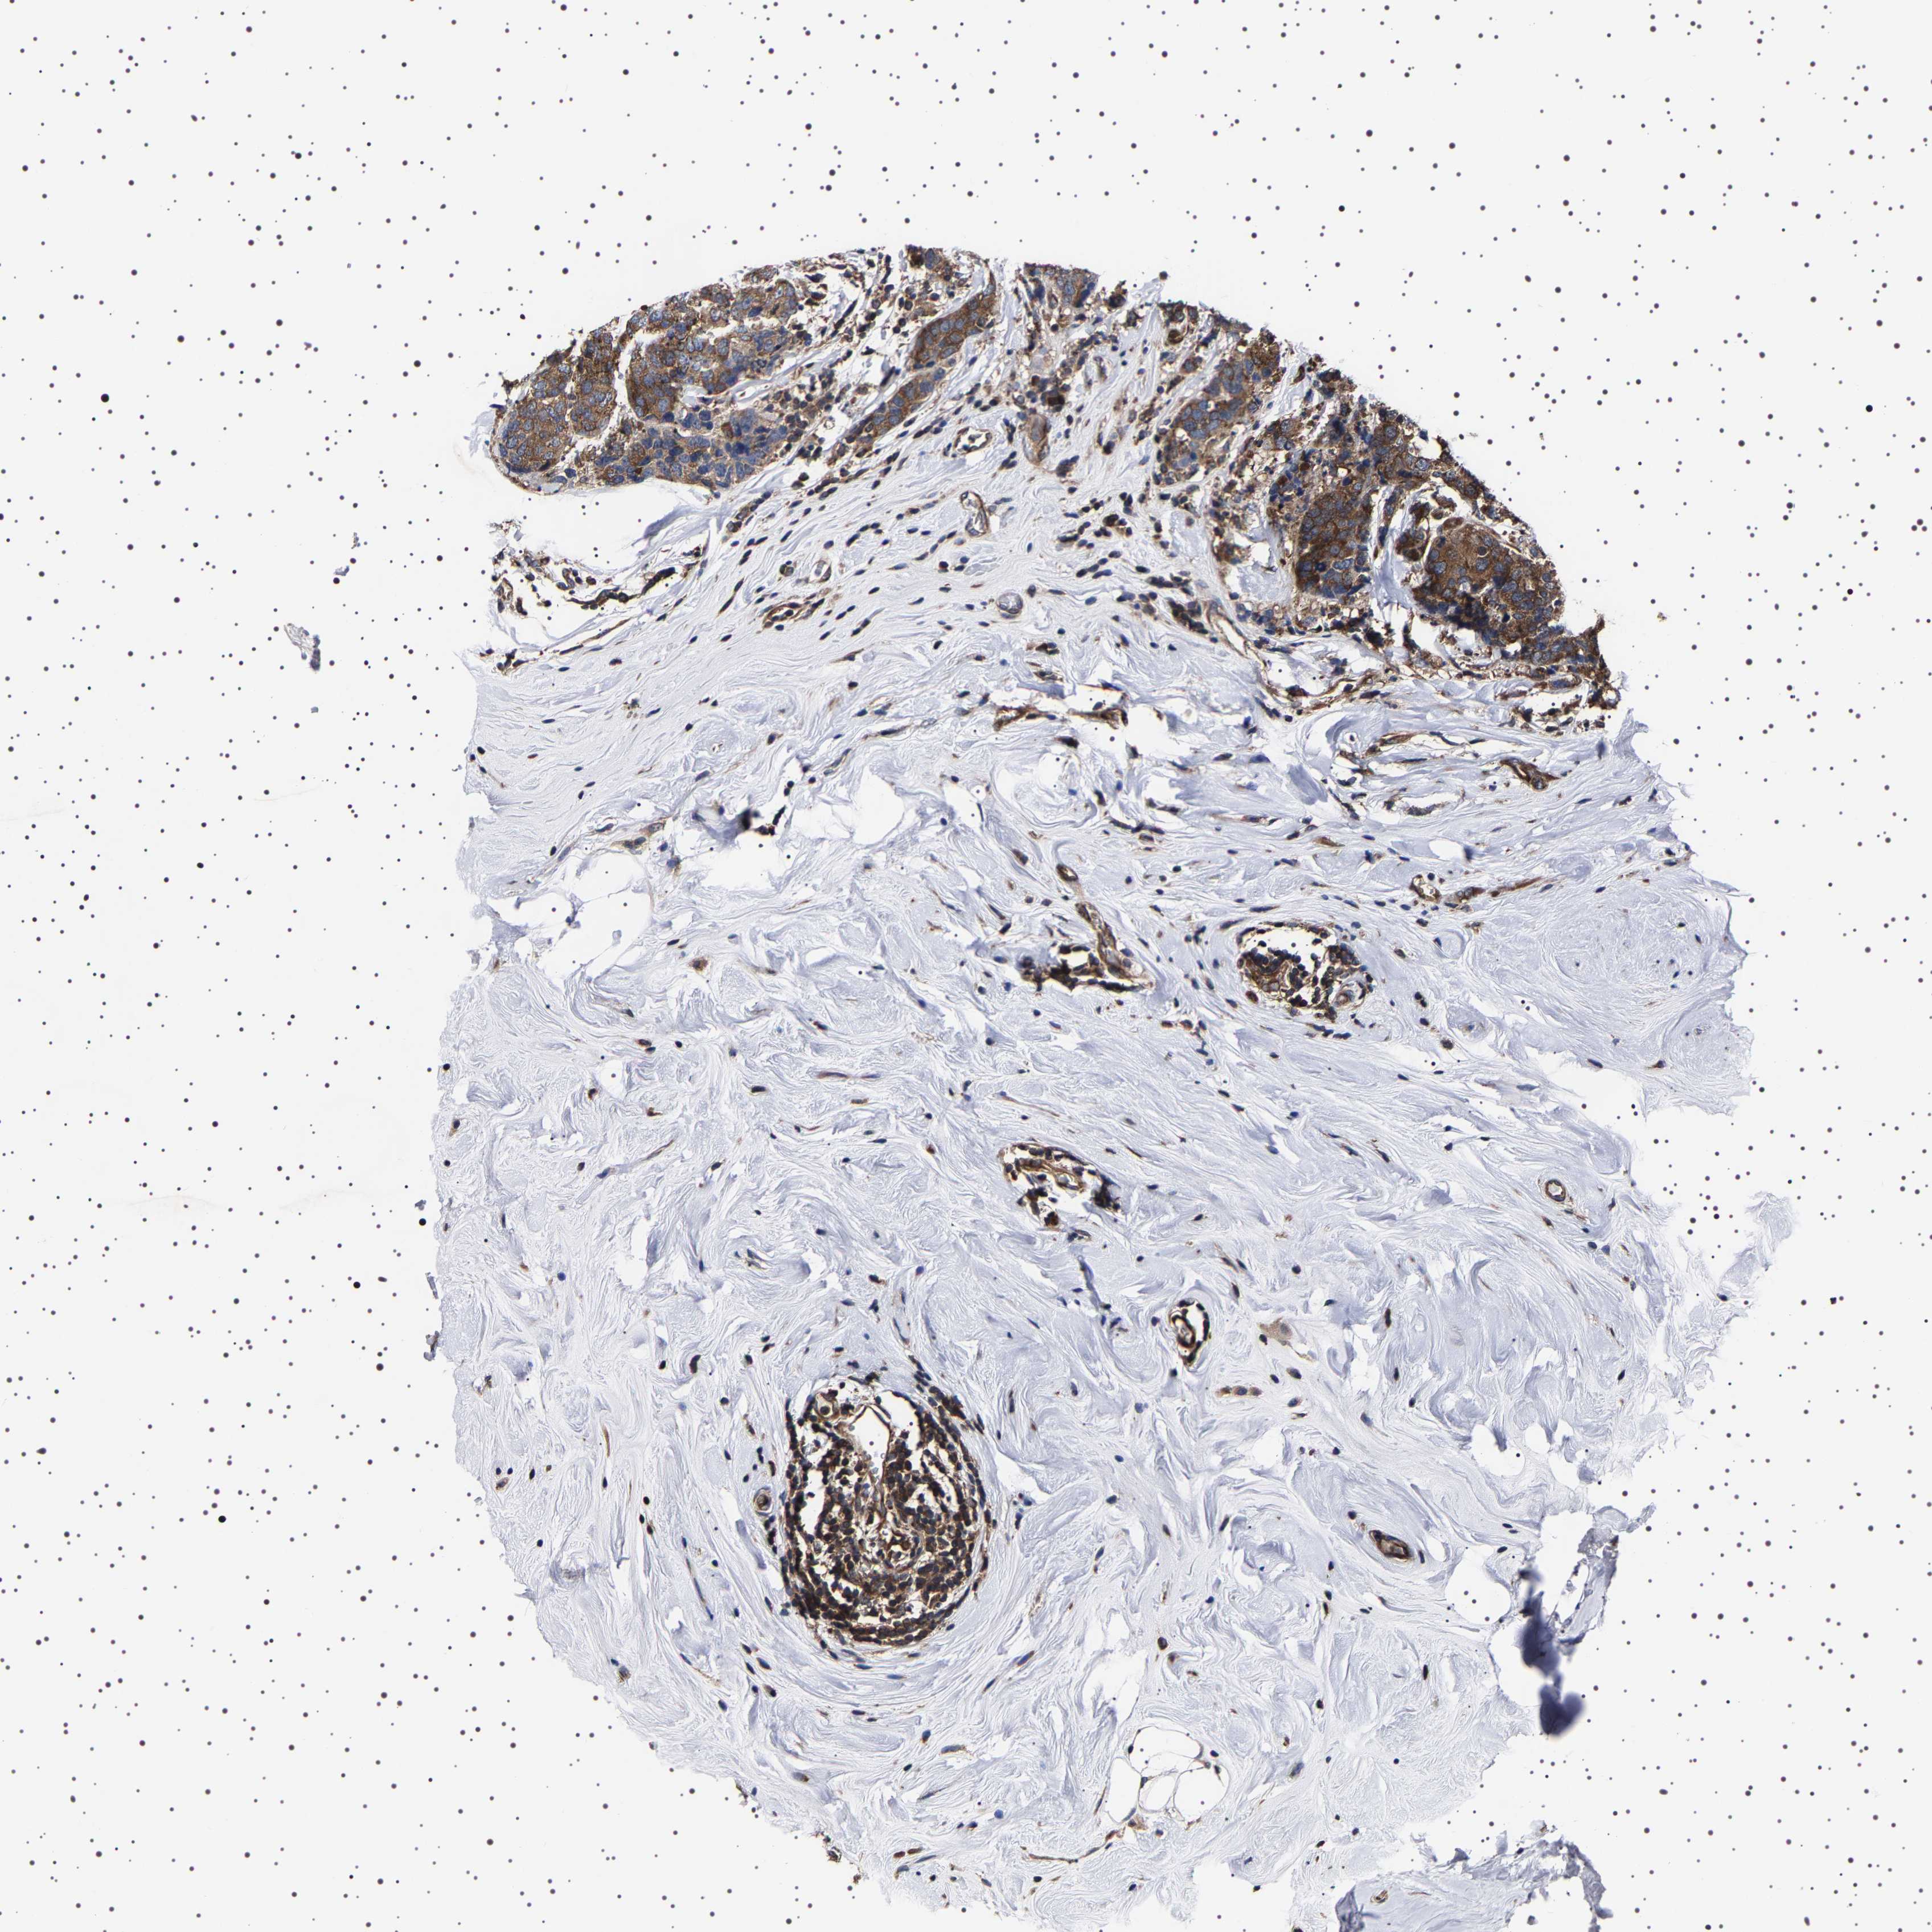

CANCER BREAST CANCER Show tissue menu

BRCA TCGA BRCA VALIDATION PROTEIN EXPRESSION